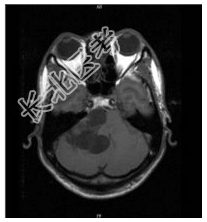

- [材料题] 患者男,37岁,右耳听力丧失数月。查体:右耳听力丧失,视力正常,余神经体征阴性。行头颅MR平扫及增强检查。